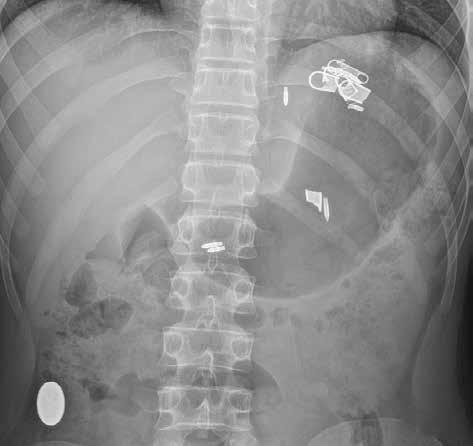

Prostý snímek břicha je stále jednou z nejlevnějších a nejdostupnějších zobrazovacích metod, využívaných při vyšetření nemocných s náhlou příhodou břišní. I když jeho význam klesá a dnes toto vyšetření nelze považovat za „metodu první volby“, má přesto i v době výpočetní tomografie (CT), ultrazvuku (UZ) a MR (magnetické rezonance) využití při podezření na střevní obstrukci či perforaci trávicí trubice, při hodnocení polohy drénů nebo detekci rentgenkontrastního tělesa (obr. 1).

Obr. 1: RTG snímek břicha vleže. Stíny několika cizích těles – pružinka, hroty propisovací tužky a úlomky zipu v žaludku. Oválný stín (knoflíku podle anamnézy) v colon ascendens.

Obr. 2, 3: RTG snímek břicha vleže a vestoje. Ileus tenkého střeva. Vleže je dobře patrná dilatace kliček tenkého střeva nad 3 cm (2). Tenké střevo odlišíme od tlustého přítomností plicae circulares, které obkružují celý obvod lumen střeva. Vstoje vidíme v tenkém střevě hladinky (3).